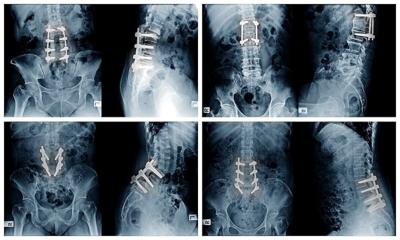

FRIDAY, Oct. 17, 2025 (HealthDay News) — The placement of orthopedic screws and rods during spinal fusion surgery should vary depending on whether you’re a man or a woman, according to a new study.

Sex-based anatomical differences in the pelvis make it essential that surgeons approach men and women differently when fusing and stabilizing the spine, researchers recently wrote in the journal Spine Deformity.

Men have a narrower pelvis, which means that screws and rods need to be placed differently for them than in women.

Specifically, it’s harder to connect screws to rods in a straight line in men, leading to additional rod bending or other adjustments during surgery, researchers said.

For the study, researchers compared 185 cases performed by three orthopedic surgeons, using X-rays and CT scans to assess screw placement and anatomical differences between male and female patients.

Results showed that the narrower pelvis in men causes rods to angle inward, rather than the parallel alignment that’s preferred.